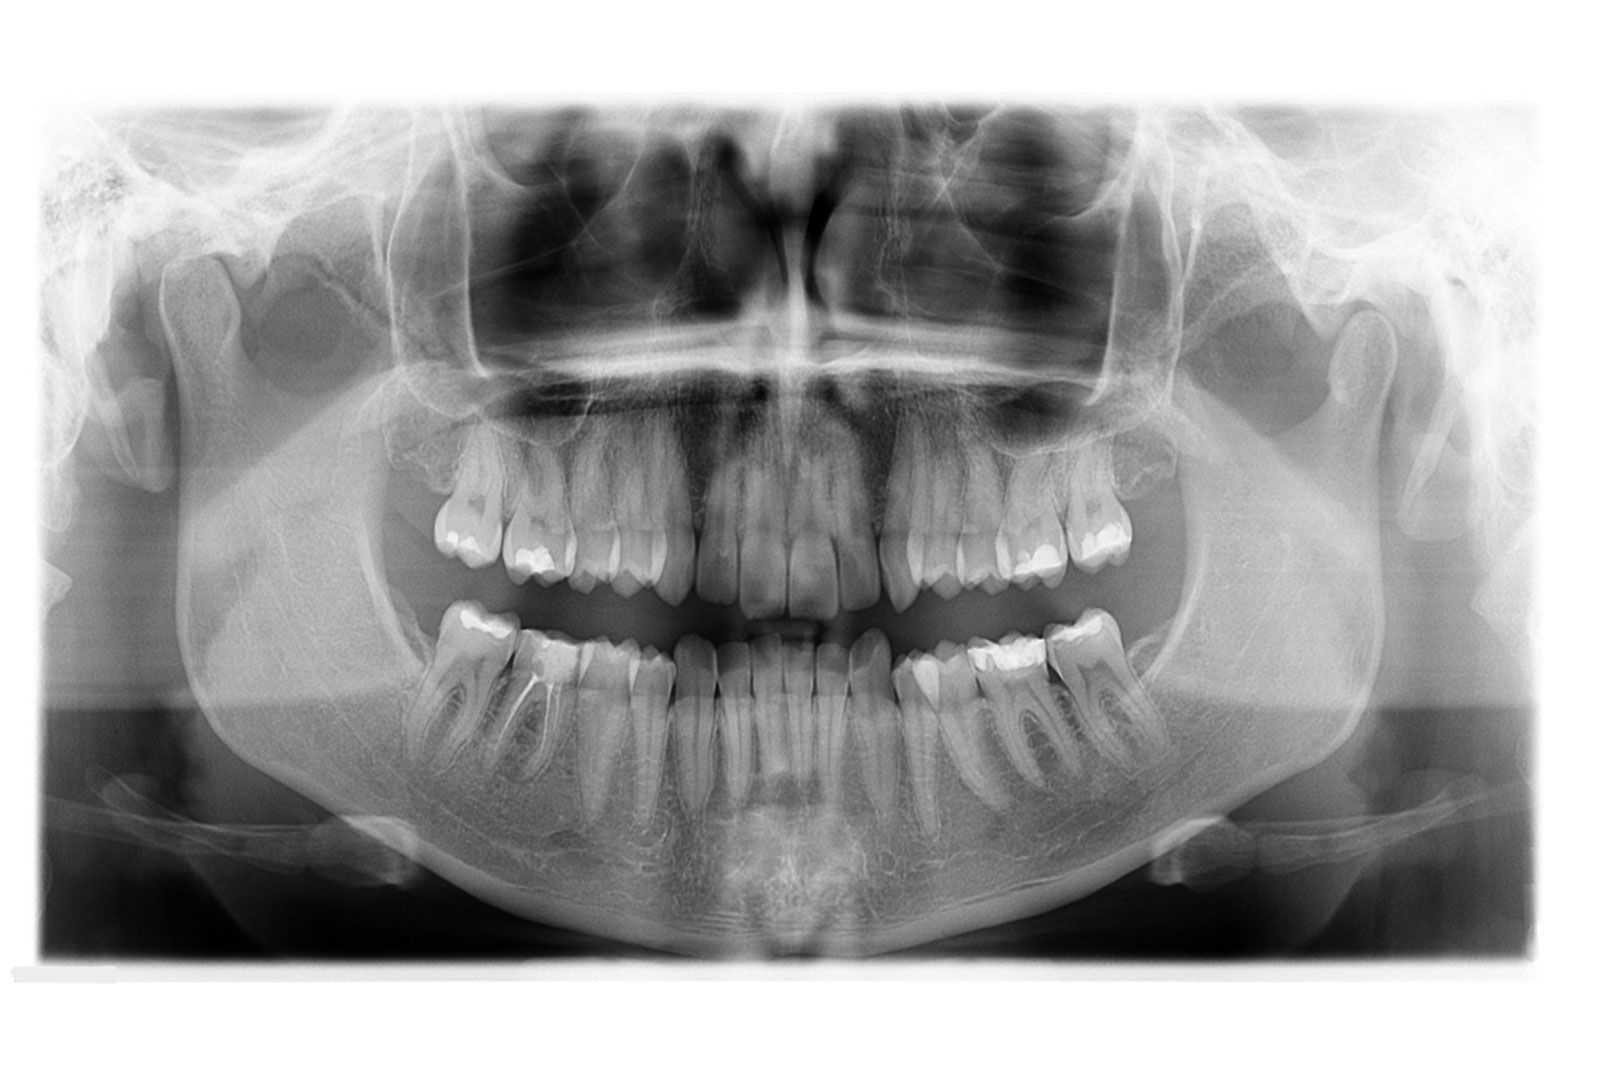

Radiologia Odontoiatrica

La sezione di radiologia odontoiatrica digitale offre servizi all'avanguardia nel campo della Diagnostica per Ortodonzia, Piantologia, Parodontologia, Chirurgia Maxillo - Facciale e Gnatologia.

Aster Diagnostica è dotata di un ortopantomografo digitale diretto, per l'esecuzione dell'ortopanoramica e del telecranio. La tecnologia diretta permette di ottenere immagini di alta qualità diagnostica a fronte di radiazioni contenute.

- Ortopanoramica